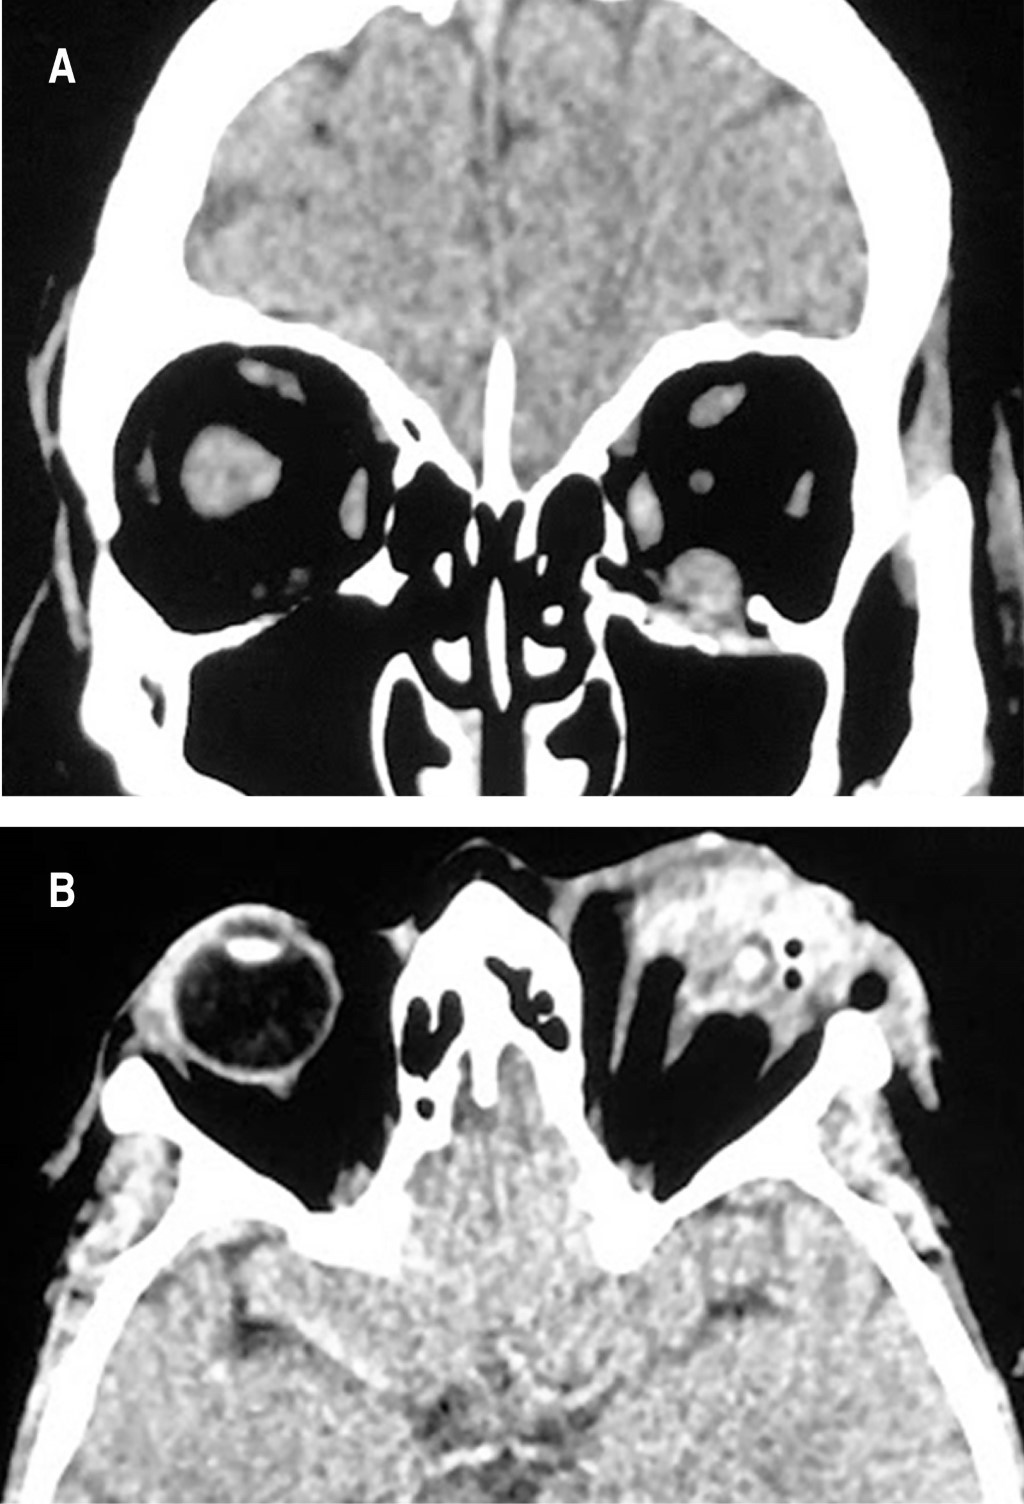

Hombre de 45 años con trauma directo por explosión de fuego artificial en región orbitaria izquierda, refiere dolor, sangrado y pérdida visual. Presenta restos hemáticos, edema y equimosis bipalpebrales. Agudeza visual en ojo izquierdo: no percepción de luz (NPL) (ojo sin visón); neurológicamente sin compromiso; la TC de órbitas muestra fractura del piso de la órbita con leve desplazamiento inferior del fragmento hacia el seno maxilar; aumento de volumen en el músculo recto inferior; y pérdida de la anotomía del globo ocular (Figura 3). Se observan laceraciones en piel, herida penetrante en ambos párpados izquierdos con involucro del margen palpebral y tarso, con heridas penetrantes en córnea, esclera con salida de iris y úvea (Figura 4). Se realiza evisceración (retiro de la córnea y todo el contenido intraocular, conservando esclera y conjuntiva), se coloca un implante esférico de ácido poliláctico (PLA) en el espacio intraescleral y cierre por planos. Inicia tratamiento tópico ocular mixto (antibiótico/esteroides), y antiinflamatorios esteroideos orales. Se decide manejo conservador de la fractura por no cumplir criterios quirúrgicos. A las seis semanas se coloca prótesis ocular cosmética.

Figura 3

Figura 4